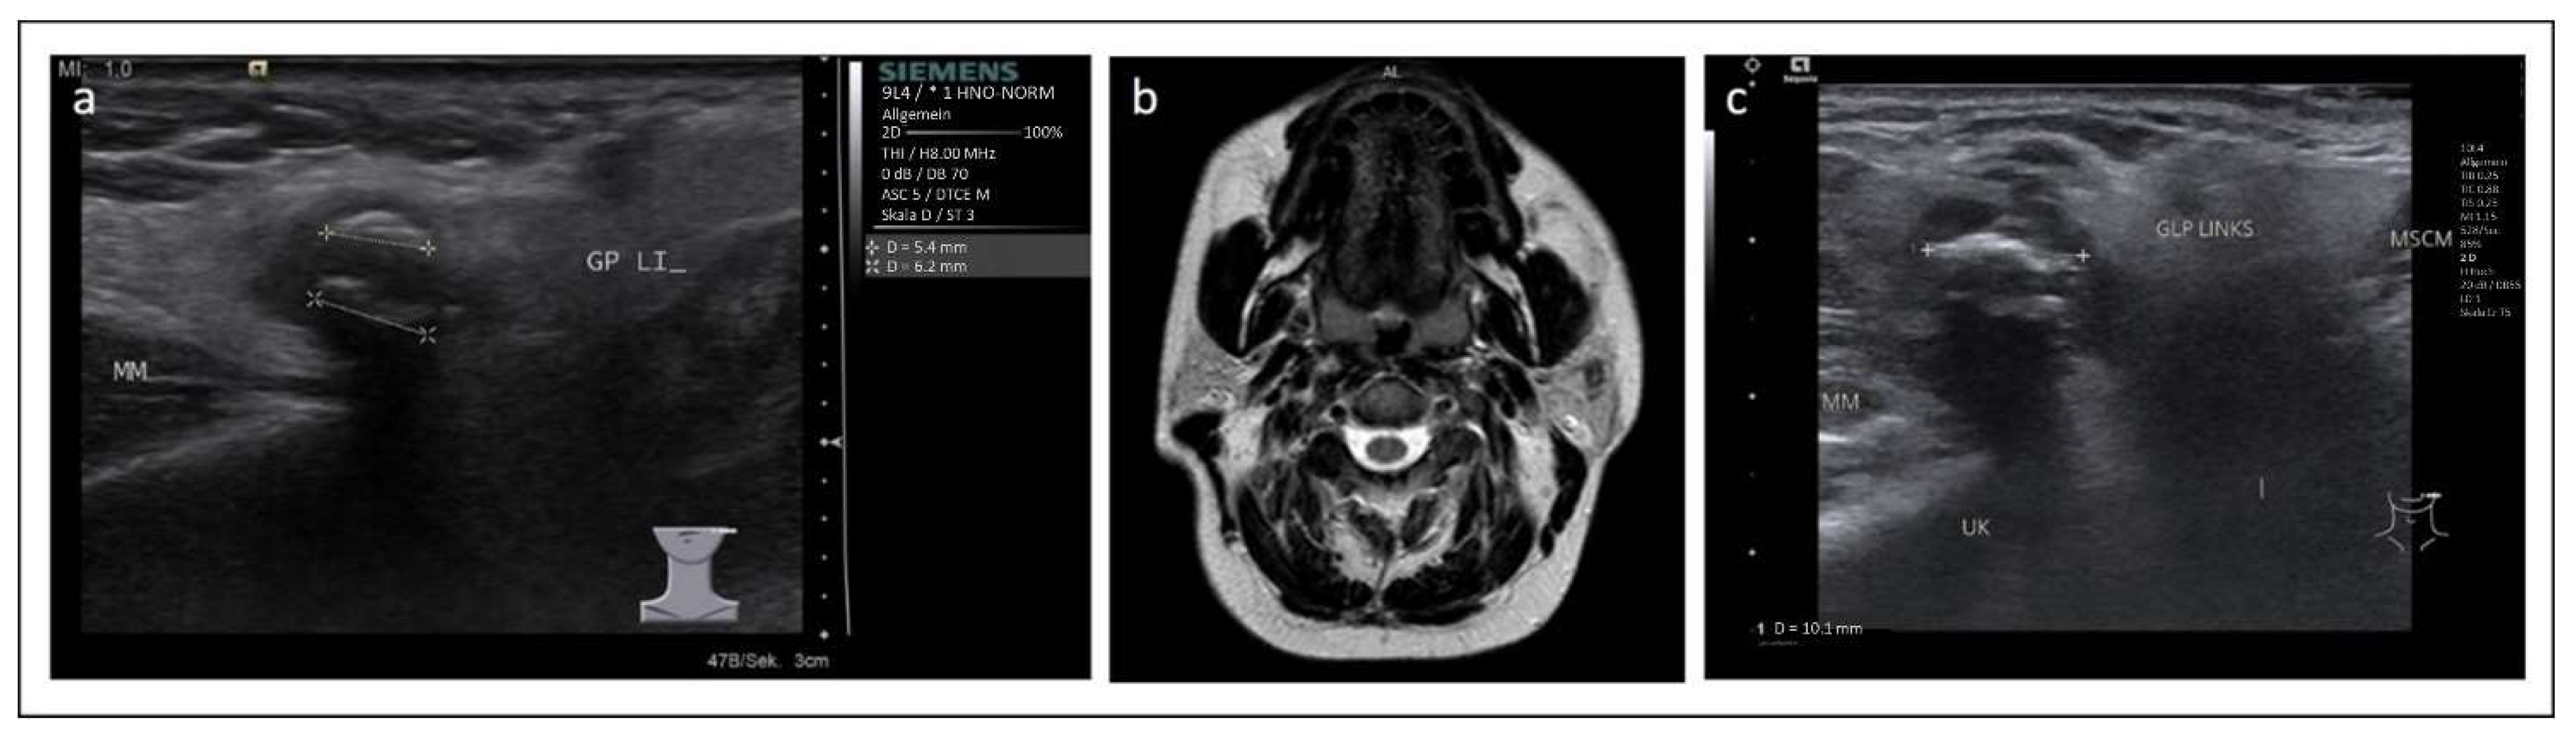

2. Case 1